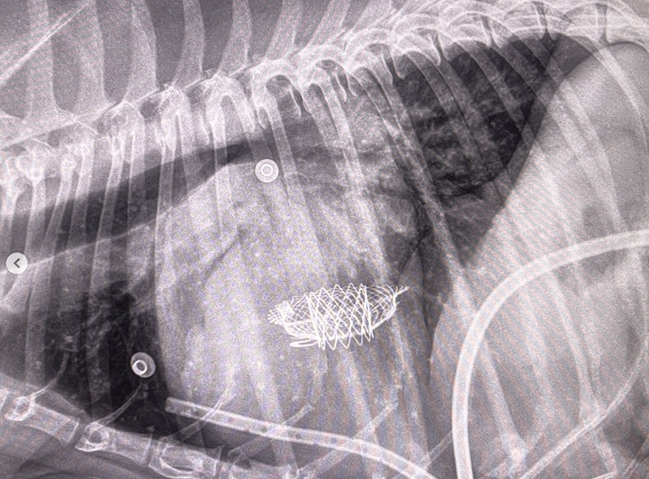

The VHS is not intended to diagnose CHF. It's purpose is to enable veterinarians to more accurately determine enlargement of the heart (called cardiomegaly or dilation) and the progression at which the enlargement is occurring, which usually is due to MVD. However, since MVD normally initially causes only the left atrium (LA) to enlarge, the VHS method is not precise enough to measure only the size of the LA. See for example, the x-ray at left, which shows that the VHS measurements entirely miss the bulbous enlarged LA in the upper right corner of the heart. (Image from Hezzell, 2018.)

The VHS method is most effective when it is used to compare two x-rays of the same dog's heart, taken over time, to see if the later x-ray's VHS value is higher than the earlier one, thus indicating that an enlargement of the heart has occurred. Therefore, once an MVD murmur is first detected, it is advisable to obtain an initial set of chest x-rays (called a "baseline" set) for comparison with subsequent x-rays once progression of the MVD is suspected.

An increase in VHS value of >0.1 per month over six months or more, in combination with a VLAS value >3.0, (see VLAS below) is evidence that the patient's heart has enlarged enough to classify it in Stage B2.

• VHS measurements to detect enlargement

Cardiologists use x-rays to evaluate the size and shape of the heart in

The Vertebral Heart

Size or Scale or Sum (VHS) is an objective means of measuring

the x-ray image above shows, using calipers, they

measure the length (from the apex to the bottom of the left mainstem) and width

(at

its widest point perpendicular to the lemgth measurement) of the heart

on a lateral x-ray and compare those dimensions

to the number of veterbrae from T4 to T12, to calculate the VHS value. Since

the dog's own vertebrae are used for comparison, each VHS value is

normalized to the dog's overall body size.